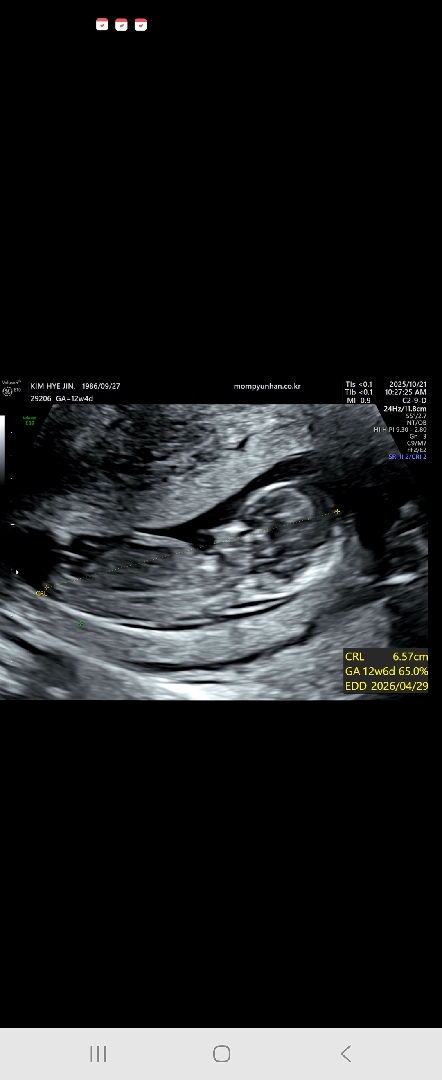

각도법좀 봐주세요

너무궁금한데 다리를꼬으고있어서 못보구왔어요 각도좀봐주세요